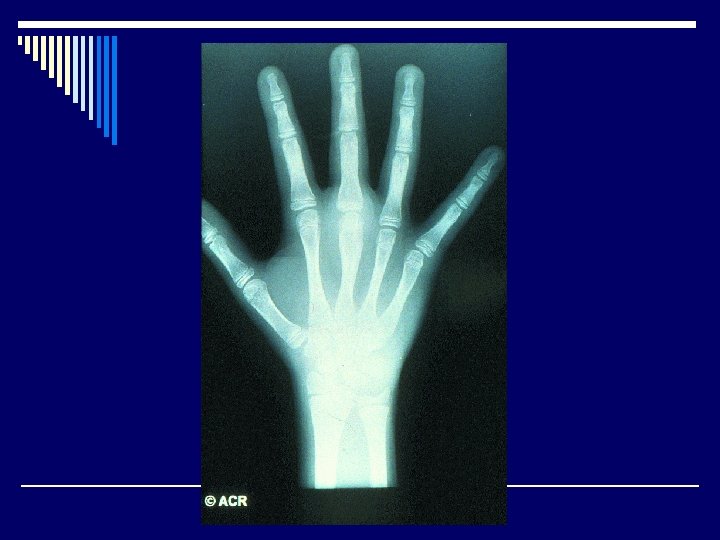

Polyarticular type o Symmetrical, large and small joints o Peak age of onset: 1 -3 years o F: M: 3 : 1 o Chronic uveitis: 5% o ANA: 40 -50% o Positive RF – 10%, increased risk of joint damage, more aggressive arthritis

Radiological features o Joint effusion o Erosion o Joint space narrowing o Joint deformity o Osteoporosis o Bony ankylosis